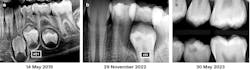

The radiographs in Figures 1a, 1b, and 1c show the tooth and the adjacent first premolar with preeruption radiolucencies indicative of carious lesions. However, no clinical evidence of occlusal caries was noted when they erupted.

A May 14, 2019, radiographic view of the patient’s unerupted first premolar showed a radiolucent defect in the mesial coronal aspect of the tooth, ostensibly subenamel (figure 1a). A buccal or lingual coronal defect could not be ruled out at that time. No such radiolucency was evident on the adjacent second premolar.

A follow-up radiograph taken on November 29, 2022, shows the primary second molar still in place; the underlying second premolar in its developmental cystic sac can be seen. It had developed a coronal radiolucency similar to that of the first premolar (figure 1b). The primary second molar was removed at that visit.

According to the radiographs, the lesions appeared to be in dentin only (figures 1a, 1b, and 1c). Although radiolucencies were evident in the mesial aspects of the occlusal surfaces of the premolar crowns at different dates pre- and posteruption (figures 1a, 1b, and 1c), no occlusal decay, enamel pits, or fissures were observed clinically after the teeth erupted (figure 2a). The radiolucencies seen in the second premolar appeared to be getting larger between November 29, 2019, and May 30, 2023. This indicates an actively progressing caries lesion, and it is doubtful that varying alignments of the radiographs can explain such enlargement (figures 1b and 1c). It is noteworthy that before root development had commenced, no radiolucency in the deeply developing second premolar crown was seen on the May 14, 2019, radiograph (figure 1a).